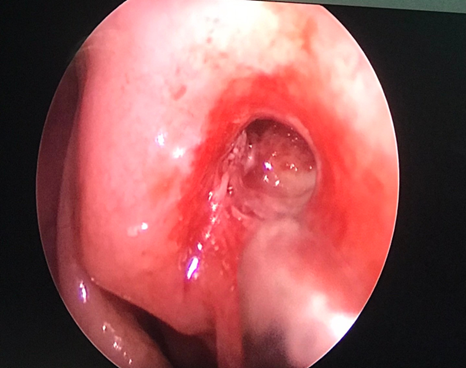

Vừa qua khoa Mắt - Bệnh viện Đa khoa tỉnh vừa tiếp nhận vầ điều trị Bệnh nhân nữ 49 tuổi vào viện vì xuất hiện khối sưng nề góc trong mắt trái kết hợp chảy mủ và chảy nước mắt nhiều. Tại đây bệnh nhân được xác định chẩn đoán Mắt trái: Viêm mủ túi lệ/ Tắc lệ đạo, bệnh nhân đã được điều trị nội khoa tích cực, triệu chứng lâm sàng giảm dần. Khoa Mắt và khoa Tai mũi họng đã kết hợp phẫu thuật cho bệnh nhân bằng phương pháp Nối thông túi lệ mũi bằng nội soi. Phẫu thuật này đã tạo đường thông trực tiếp từ túi lệ sang khoang mũi nhằm dẫn nước mắt từ mắt sang mũi. Sau phẫu thuật 2 ngày, các triệu chứng lâm sàng của bệnh nhân thuyên giảm và được ra viện sớm.

Hình 2. Mở lổ thông từ túi lệ-khoang mũi